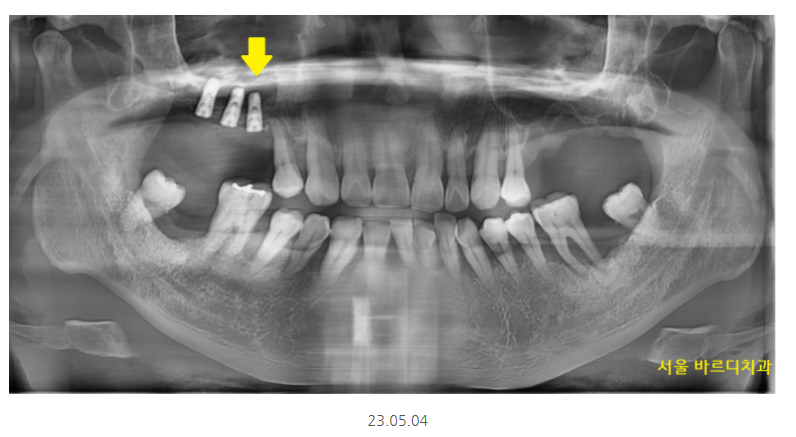

오늘 소개해드릴 환자분

하루 2갑씩 피는 환자분이셨습니다.

환자분을 처음 뵈었을 때

솔직히 말씀드려 안 흔들리는 치아가 없었습니다.

잇몸이 많이 망가졌어요.

윗니는 개수로만 4개 없음

아랫니는 2개 없음

이건 이미 뽑힌 상태만 세었을 때이고

뽑을 치아도 상당했습니다.

윗니 어금니 부분 예시를 보여드리면..

어금니 대부분이 잇몸뼈가 거의 없어서

뿌리만 잡고 있는 정도였거든요~

상악동까지 거리 3.4mm

임플란트는 최소 8mm정도 심으니까

만들어야할 양만해도 5mm가 넘네요.